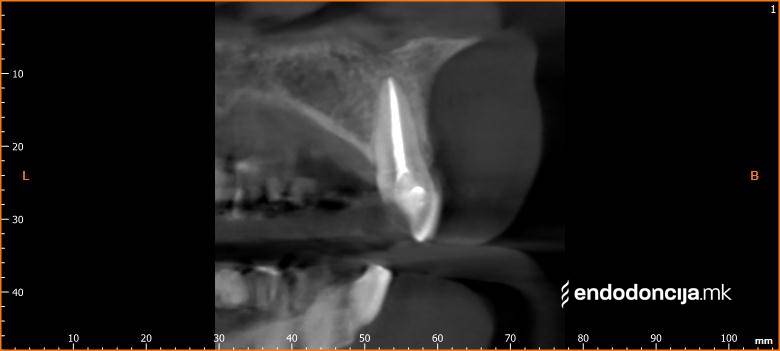

Κατά τη διάρκεια της επεξεργασίας του ριζικού σωλήνα, τα λεπτά όργανα ενδέχεται να σπάσουν. Αυτό μπορεί να αποτελέσει εμπόδιο για την πλήρη προετοιμασία και τον καθαρισμό του ριζικού σωλήνα. Με μια μικροσκοπική επεξεργασία του ριζικού σωλήνα μπορεί να είναι δυνατή η απομάκρυνσή τους υπό ορισμένες συνθήκες, χωρίς να καταστρέφεται η ουσία των δοντιών.